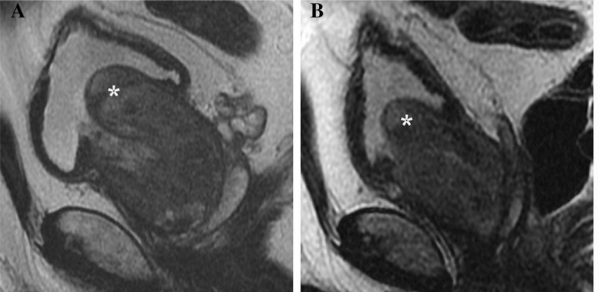

圖二:治療前後體積變化

左圖是治療前,右圖是治療後,治療後攝護腺體積明顯縮小,且攝護腺突出至膀胱內的部分(星號)也有顯著縮小。